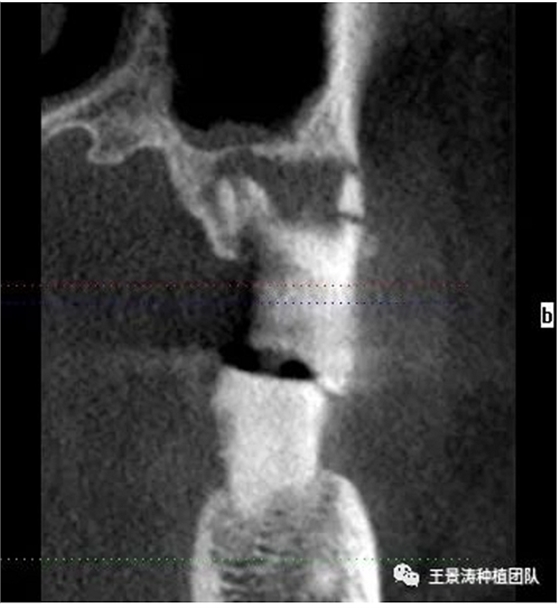

下述病例則是15區(qū)域的即刻種植,15因牙冠折斷于齦下,無法樁核冠修復(fù),則考慮種植修復(fù)。但拍攝CBCT后發(fā)現(xiàn)根尖距上頜竇底距離較短。患者為年輕女性,無全身系統(tǒng)疾病且可利用上頜竇底與根尖皮質(zhì)骨雙側(cè)皮質(zhì)骨固位,且此位置可通過頰側(cè)軟組織減張技術(shù)獲得嚴(yán)密封閉牙槽窩。因其根尖距上頜竇距離較低,遂拔除15后行上頜竇內(nèi)提升,埋入式種植,最終修復(fù)的完成。

其次初期穩(wěn)定性的獲得,前牙美學(xué)區(qū)種植體的初期穩(wěn)定性主要是依靠腭舌側(cè)骨板及基底骨來獲得的。后牙區(qū)的穩(wěn)定性主要依靠多根牙的牙槽間隔及根尖到重要解剖位置的高度的骨質(zhì)獲得(主要是竇嵴距和管嵴矩的高度,還要參考植入種植體的長度),因此術(shù)前仔細(xì)測量牙槽間隔與根尖至重要解剖結(jié)構(gòu)的高度是后牙即刻種植的關(guān)鍵因素之一。